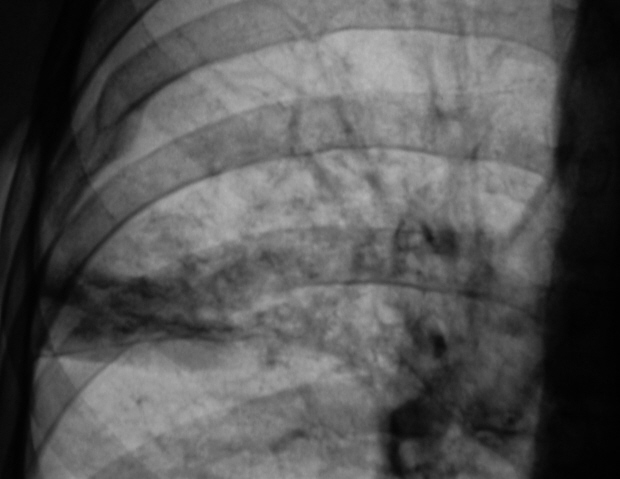

Что такое малоконтрастная рентгенограмма органов грудной клетки